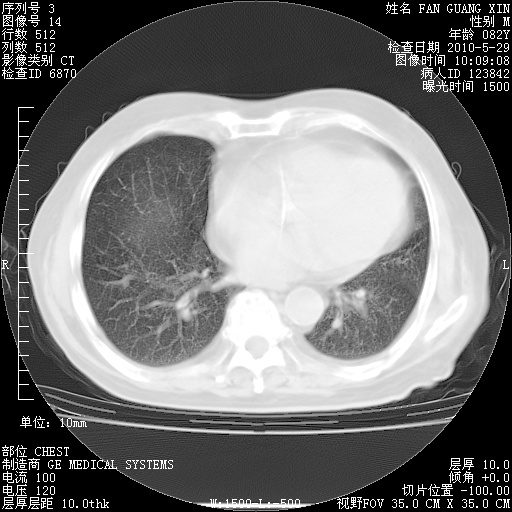

再治疗10天后的肺部CT